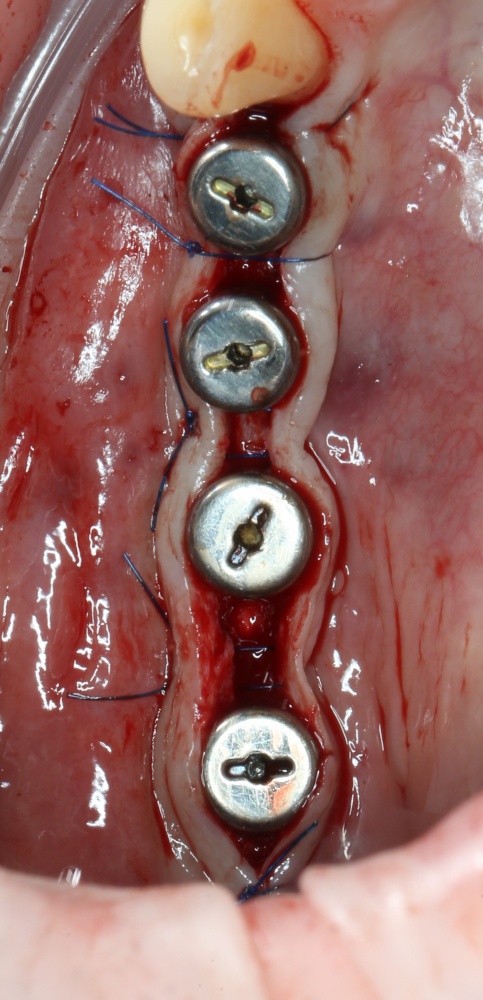

Если на этапе разреза и формирования раны всё сделано правильно, то наложение швов не вызывает особых трудностей. Периостотомия или послабляющие разрезы на периосте не требуются (ни практически никогда не требуются). А сами швы получаются аккуратными и герметичными:

Обрати внимание, что все шовные лигатуры находятся в пределах кератинизированной десны. Это позволяет избежать деформации тканей и лишних рубцов. В наиболее уязвимых местах (около зубов) шовные лигатуры лучше продублировать.

Если бы мне пришлось делать это сейчас, то я бы использовал непрерывный «матрацный» шов. Он удобнее, быстрее в наложении и комфортнее для пациента. Минус — если распускается, то распускается весь. К тому же, его очень неудобно снимать.

Несмотря на то, что уже тогда мы широко использовали непрерывные швы в подобных случаях, здесь я, во-первых, зассал (может распуститься), во-вторых, снятие швов предполагалось в поликлинике по месту жительства пациентки, и мне не хотелось, чтобы там при снятии швов начудили. Как выяснится позже — зря беспокоился.

Неизменно одно — в таких операциях мы использовали и до сих пор используем нерезорбируемые монофиламентные шовные материалы, поскольку они наиболее гигиеничные. Чтобы острые концы нитей не беспокоили пациента, их можно оплавить нагретой гладилкой или гуттаперчевым плаггером.